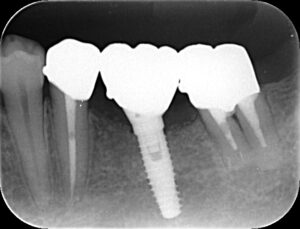

インプラントとは失った歯の部分にチタン製の人工歯根を埋め込み、その上にかぶせ物を装着する治療です。

*この患者さんは奥から2番目をインプラント治療しています